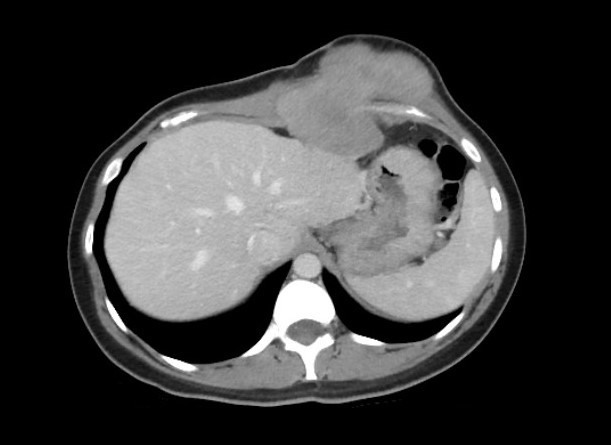

A 34-year-old female patient with history of resection of an abdominal wall desmoid tumor and reconstruction with a component separation technique presented 12 months after surgery reporting pain adjacent to the surgical site, which was ultimately determined to be a local recurrence. The resection of the recurrence included the tumor (approximately 12 × 10 × 10 cm), skin, the cartilaginous sections of the seventh and eighth left costal arches, omentum left anterior leaflet of the diaphragm, and the medial half of the right rectus abdominis muscle (Figure 1). The abdominal wall defect was reconstructed by placing a 15 × 18-cm 2-component mesh fixed to the aponeurosis. In addition, a small defect was created at the superior edge of the mesh, through which a pedicled omentum flap was exteriorized. Four weeks later, the patient developed mesh exposure and peritoneal-cutaneous communication (Figure 2).

Figure 1. Recurrent multilobed abdominal wall desmoid tumor. The resection included the tumor, the overlying skin anteriorly, the cartilaginous sections of the seventh and eighth left costal arches, partially the omentum and left anterior leaflet of the diaphragm, and the medial half of the right rectus abdominis muscle posteriorly.